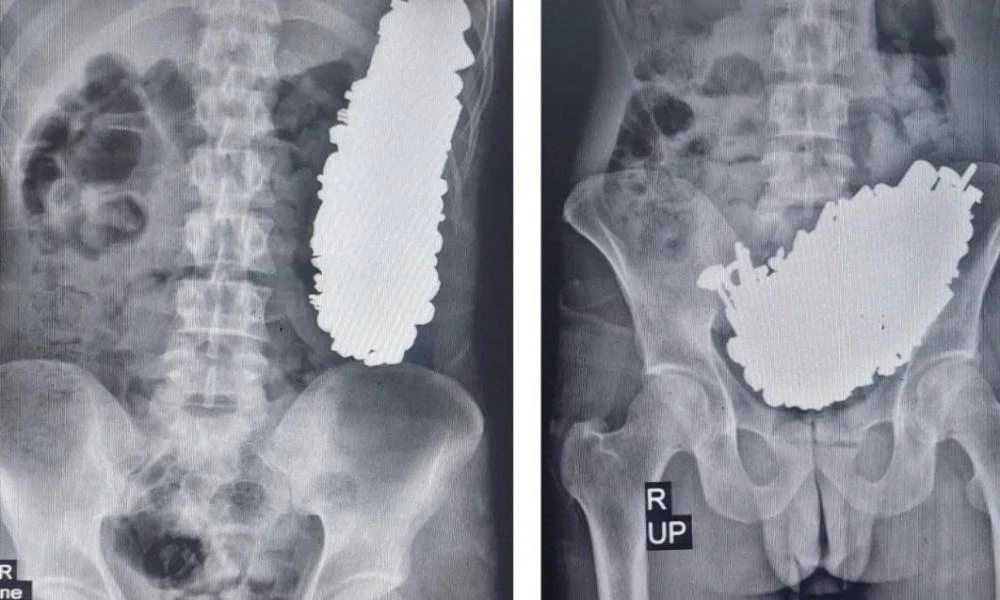

Ιράν: Άνδρας είχε καταπιεί 450 μεταλλικά αντικείμενα - Μετά την επέμβαση αφαίρεσής τους, οδηγήθηκε σε... ψυχιατρείο

Μια σπάνια περίπτωση επιτυχούς αφαίρεσης περισσότερων από 450 τεμαχίων μεταλλικών αντικειμένων από το στομάχι ενός 37χρονου άνδρα μέσω κατάποσης ξένων σωμάτων, στο νοσοκομείο Imam Khomeini στο Ahvaz τ...